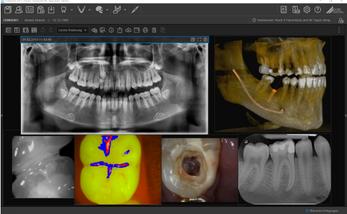

The intelligent interchangeable head mechanism offers many different potential applications Whether for macro or intraoral imaging, VistaCam iX will assist you with caries diagnosis, early detection and plaque visualisation

Maximum flexibility for your diagnoses Hyperion X9 pro is fully configurable and its modular and scalable design makes it possible to transition from a basic to a more advanced version in an easy and costeffective manner. An extraordinary platform that adapts to the needs of your dental practice thanks to the 2D PAN/CEPH sensor, which can be easily relocated, and the reversible teleradiographic arm which can be installed on both sides Moreover, the standard 2D sensor can be replaced with the innovative direct conversion DCIII sensor to provide SuperHD images with low doses The most versatile extra-oral 3-in-1 imaging device on the market. Perfect for ultra-high quality 2D and 3D exams with very low doses

FOVs with a 10 cm diameter are essential for the study of impacted third molars because, in an adult of medium build, the distance between the third molars on the left and right, including the respective roots, the alveolar process and the surrounding bone, is at least 9 cm Reduced fields of view are useful when analysing impacted or supernumerary teeth in order to restrain the dose to the region of interest For a correct treatment planning it is indeed crucial to determine the actual position (vestibular or palatal) This is only possible with a 3D analysis, even at a very low dose, with the QuickSCAN protocol The complete 13 x 16 cm field of view allows for an accurate assessment of the upper airways, which is often useful to complete the investigation for an orthodontic treatment that does not neglect ENT problems.

Position the equipment directly on the 3D model, combine it with the STL data from intraoral scanners and define the final prosthetic project With the advanced implant planning tools* you will be able to operate safely thanks to accurate information on the amount of bone and the distance from the surrounding anatomical structures, such as the mandibular canal, defining a minimum safety distance

Innovative DCIII technology, which improves depth of field and increases contrast - and therefore real resolution power - lets users obtain SuperHD panoramic images from extremely extensive datasets to provide an 11-layer MultiPAN. Highly useful in the case of complex morphologies